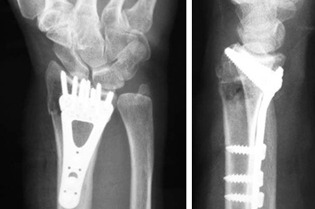

This past Tuesday 8/7 I had metal plate and screws put in right wrist. Yesterday, they performed the same procedure on my left wrist.